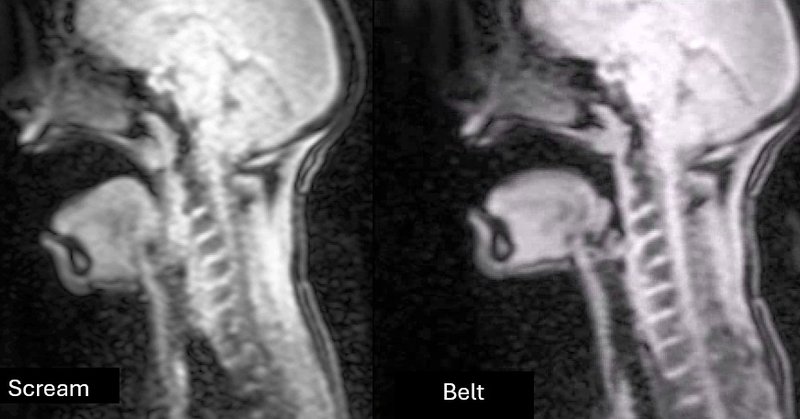

Link above is the popular version of “Physiologic and acoustic characteristics of the angry scream” presented at the 189th ASA Meeting

“The science of screaming” by Karen Perta, Zhaoyan Zhang, Donna Erickson, Ryoko Hayashi and Toshiyuki Sadanobu (Nov. ’25)

The purpose of this study is to analyze and compare angry, emotional screaming with trained, “healthy” yelling using MRI and acoustic measures.